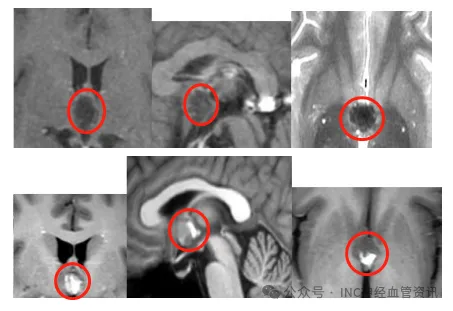

该头痛具有独特临床表现:起床活动后30分钟内症状可缓解,但重...

3岁女童阿莉莎突发剧烈头痛伴呕吐症状,起病无明显前兆。病情...

儿童偶发头痛发热虽属常见,但本次症状表现截然不同——病情...